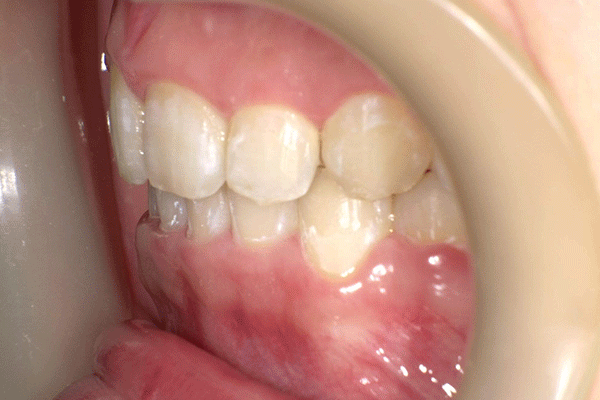

治療前

治療後

主訴:上顎前歯部叢生 診断:アングルⅠ級 年齢:18歳

用いた装置:側方拡大装置、エッジワイズブラケット

抜歯部位:非抜歯 治療期間:1年3ヶ月

治療費:約79万円 リスク:特になし